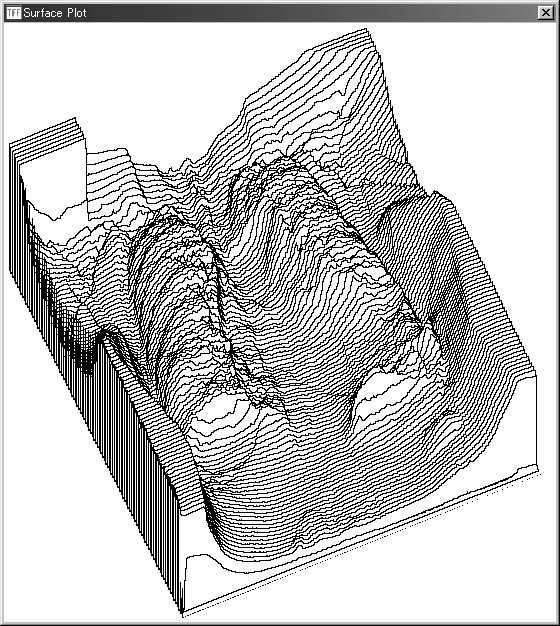

D. Surface Plot(表面モデルの表示)

「Surface Plot」では,選択した領域のプロファイルを三次元的に観察できる表面(Surface)モデルを表示する(図5-5).表面モデルとは,画素値を画像の濃淡ではなく,z軸方向の高さで表現したもので,図に示されるように,画像の三次元的な形状を見ることができる.

図5-5 「Surface Plot」によるChest画像の表面モデルの表示例